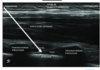

Cross sectional drawing of interscalene block

Nb C5, C6 + C6 and C7 make up traffic lights

veterbral artery at c7 transverse process

phrenic nerve passes over anterior scalene away from c5